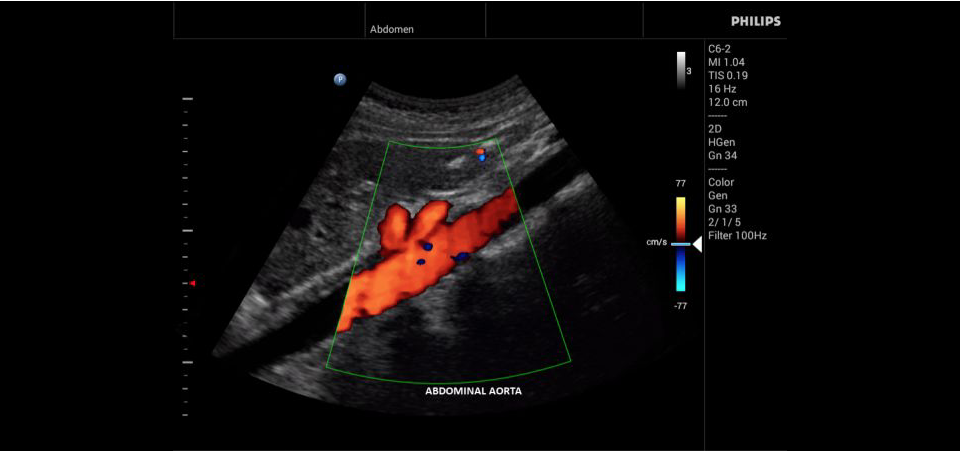

• Общие абдоминальные исследования;

• Исследования сосудов;

• Цветное допплеровское картирование

• Конвексный УЗИ датчик Philips С6-2